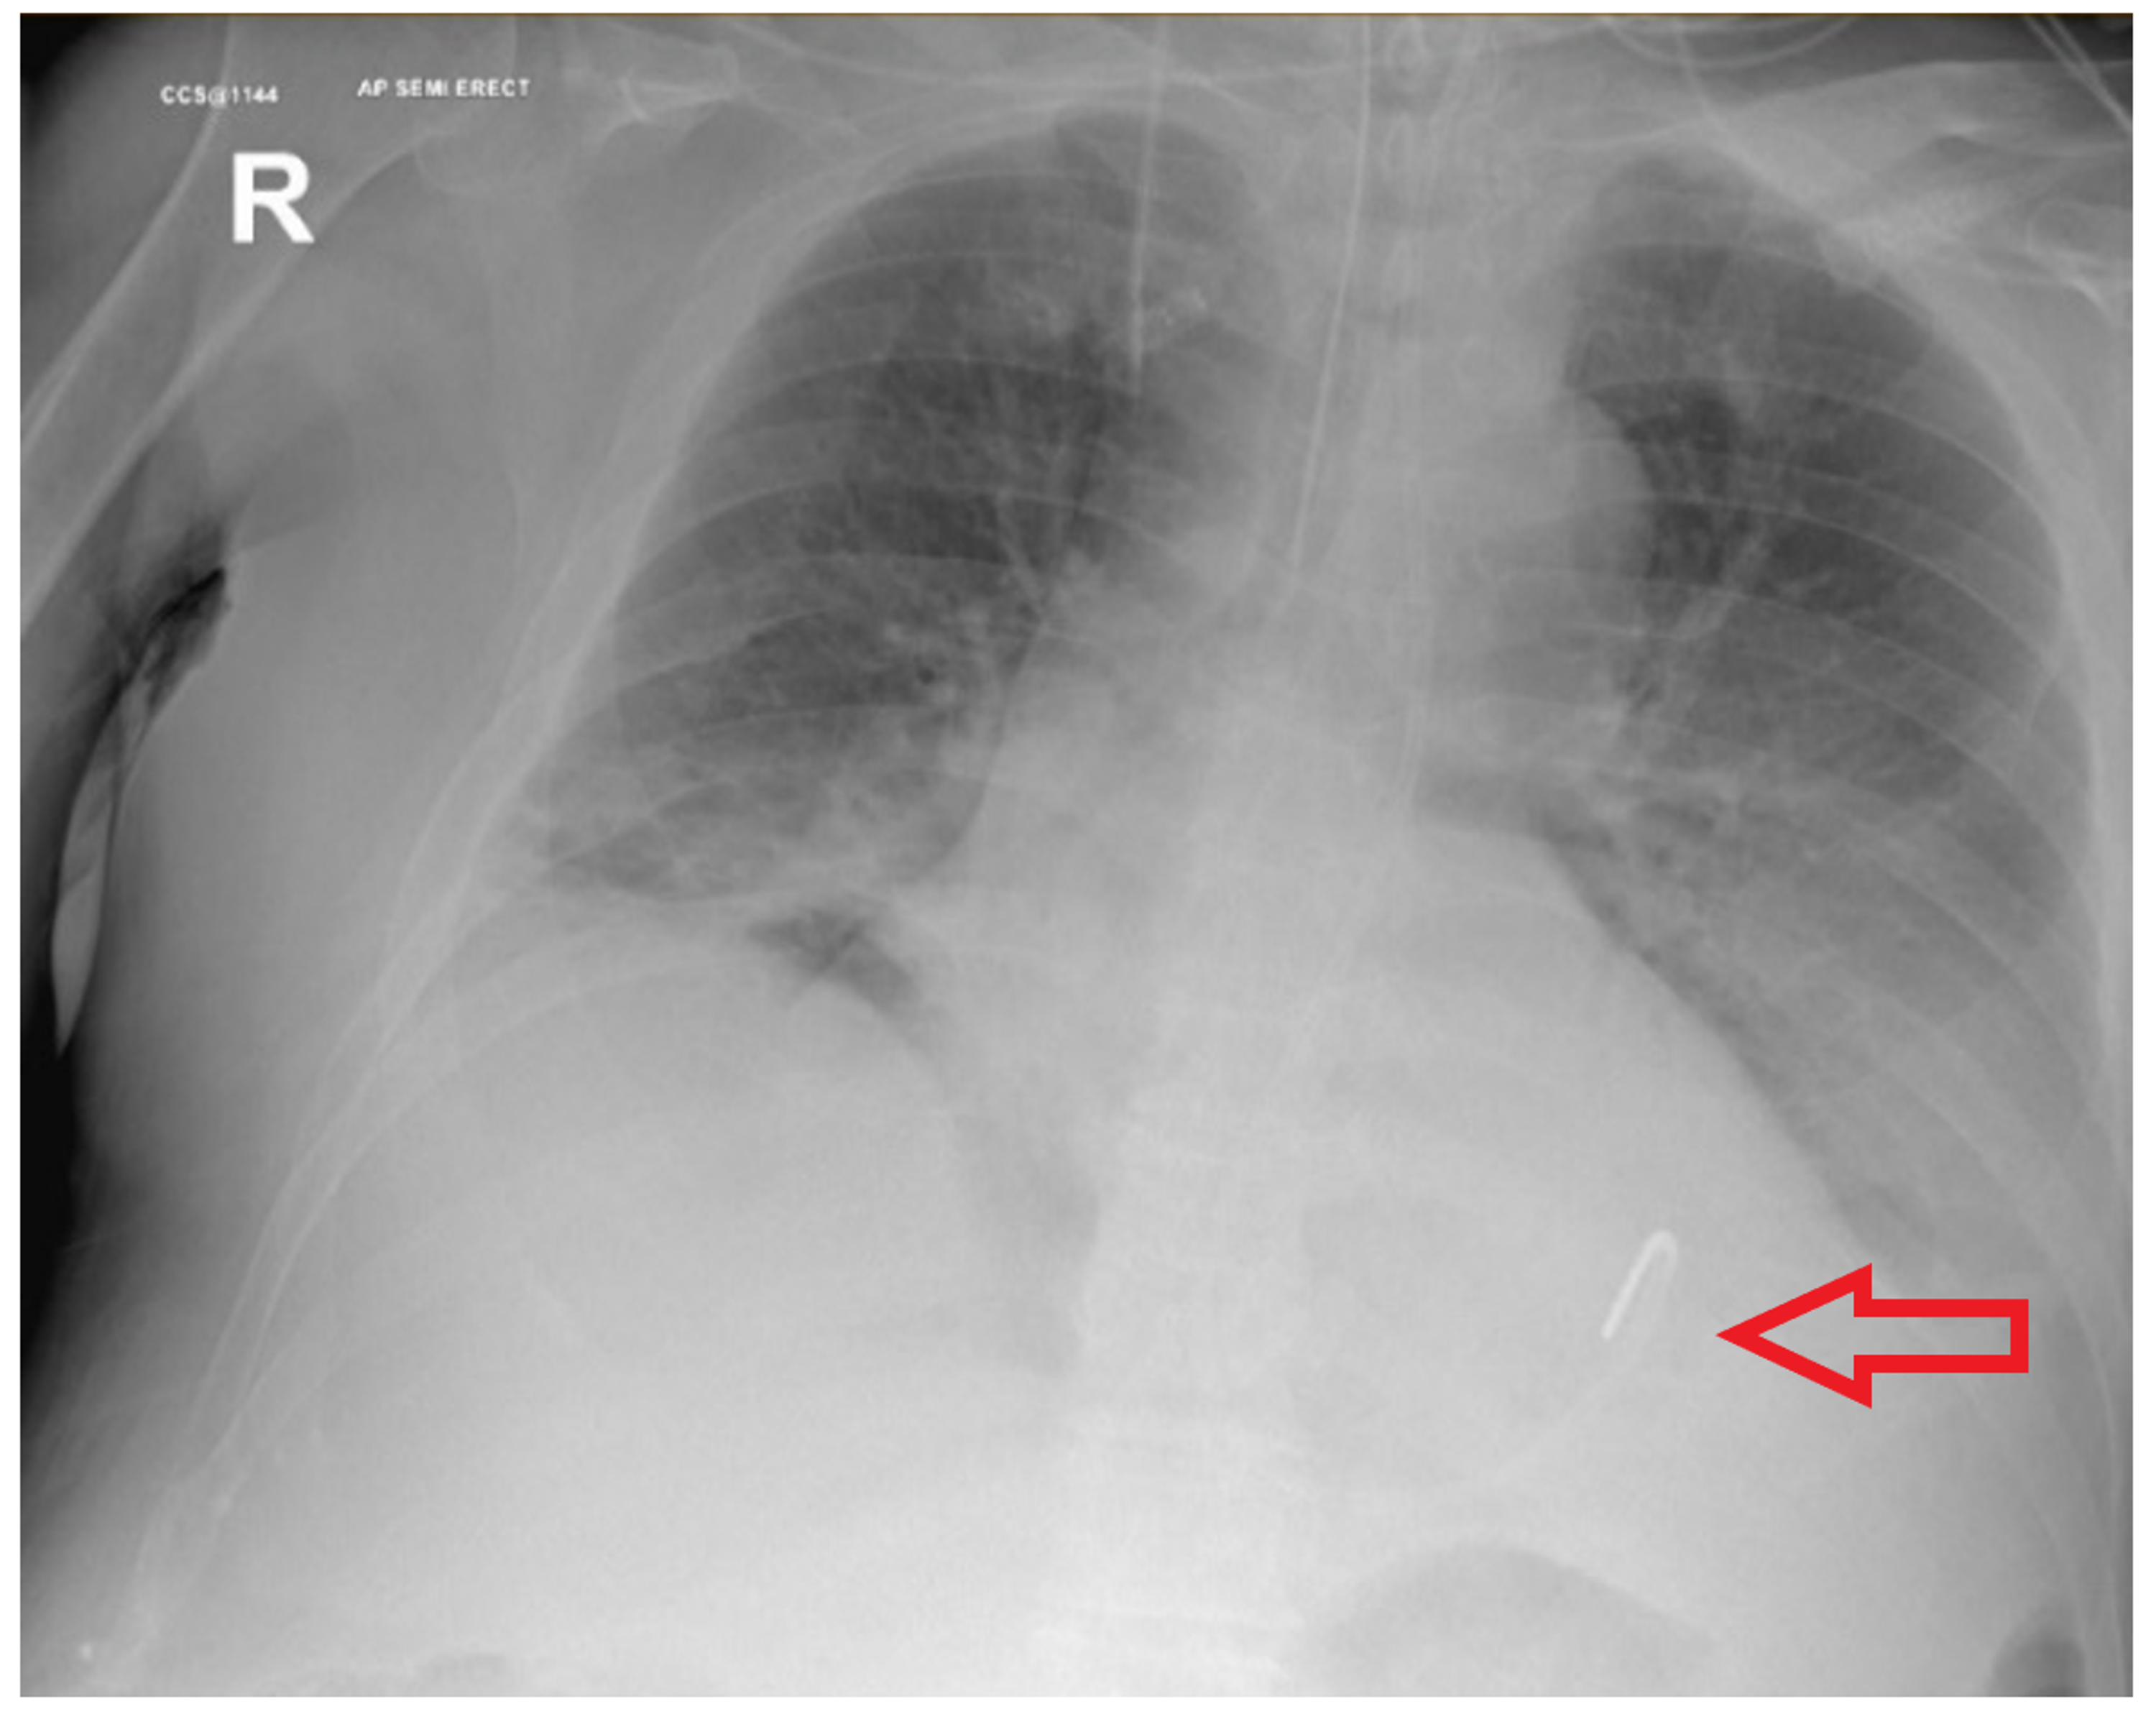

Gastrointestinal perforation occurs when a hole forms all the way through the stomach large bowel or small intestine according to Healthline. 81 Age is a known independent factor for complications in colonoscopy. The aim of this work is to analyze the therapeutical approach of emergency gastric ulcer complications in elderly patients in order to establish the factors affecting the morbidity. The mainstay of treatment for intestinal perforation is surgery. Gastrointestinal perforation is a hole in the wall of the gastrointestinal tract.

Morbidity and mortality from small bowel obstruction in elderly is high. Gastro duodenal perforations were found in 5 cases of perforated duodenal ulcer 3 cases of perforated gastric ulcer 1 case of duodenal perforation due to gallbladder cancer invasion and 1 case of iatrogenic gastric perforation caused by guide-wire of a long tube using for intestinal obstruction. Gastrointestinal perforation is a hole in the wall of the gastrointestinal tract. Although perforation is a rare complication 13 carrying a 5071 mortality rate the risk increases up to 23 when caecal diameter is 14 cm 11. Gastrointestinal perforation occurs when a hole forms all the way through the stomach large bowel or small intestine according to Healthline.